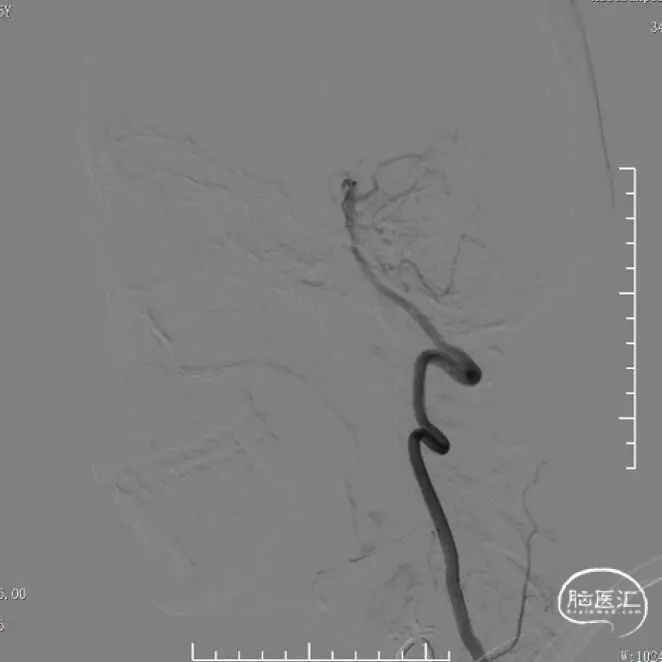

全麻下,通过同轴技术泥鳅导丝、5F VTK将6F长鞘置于右侧颈总动脉,撤出微导丝及VTK,随后路图下泥鳅导丝携6F Tethys®中间导引导管置于右侧颈内动脉C4段。撤出泥鳅导丝,在6F Tethys®中间导引导管路图下,顺导丝(交换导丝)将加奇SacSpeed® 1.75×12mm球囊置于狭窄段,路图下精确定位,以1atm/30s速度缓慢扩张球囊至6atm左右,释放球囊压力。造影提示右侧大脑中动脉狭窄明显改善,瘤样突起减少,撤出球囊。